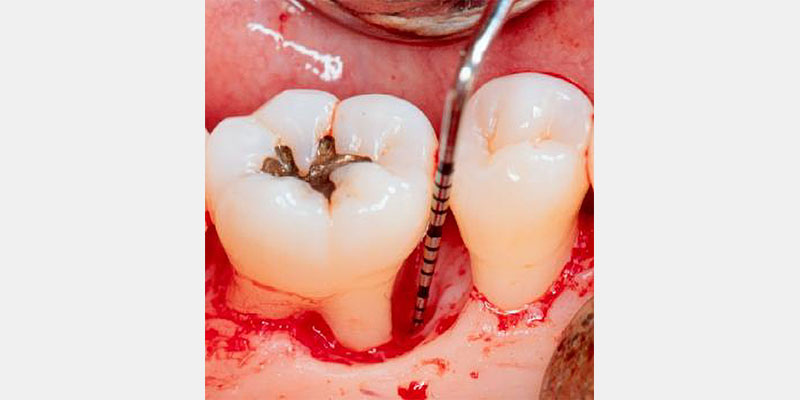

Periodontal regeneration includes the recreating of periodontal ligament, cementum and alveolar bone along the previously diseased and denuded root surface. The evidence supporting guided tissue regeneration is vast and growing. For decades dental surgeons have been using, with high levels of predictability, resorbable and non-resorbable barrier membranes in passive tissue engineering around teeth and dental implant dehiscence and fenestrations.3, 4 By employing active tissue engineering, new levels of predictability and success can be reached to resolve hard and soft tissue, periodontal and other orofacial defects.

Periodontal defects include the intrabony and furcation-type defects, as well as with gingival recession or loss of attachment. The periodontal literature validates the regenerative potential of biologically active bone replacement grafts (Figs. 1–5).5, 6, 7 Periodontal regeneration with histological evidence of new cementum, periodontal ligament and alveolar bone has been shown in the human model with a recombinant growth factor and a porcine (pig)-derived protein.8, 9, 10

The ability to reconstruct the tissues in an area that was previously infected by periodontitis serves as the ultimate acid test for regenerative achievement. Human recombinant platelet-derived growth factor (PDGF-BB), a protein that regulates cell growth and division, and beta tricalcium phosphate (β-TCP), a drug delivery system for bone, have been shown to accelerate clinical attachment level gains and significantly increase bone growth in severe periodontal defects.11 Recombinant human platelet-derived growth factor (rhPDGF-BB) and enamel matrix derivative (EMD) have demonstrated tissue regeneration when used adjacent to a previously diseased root surface.8, 9, 10